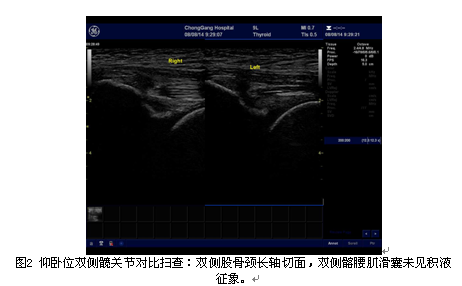

高频超声观察退行性髋关节病